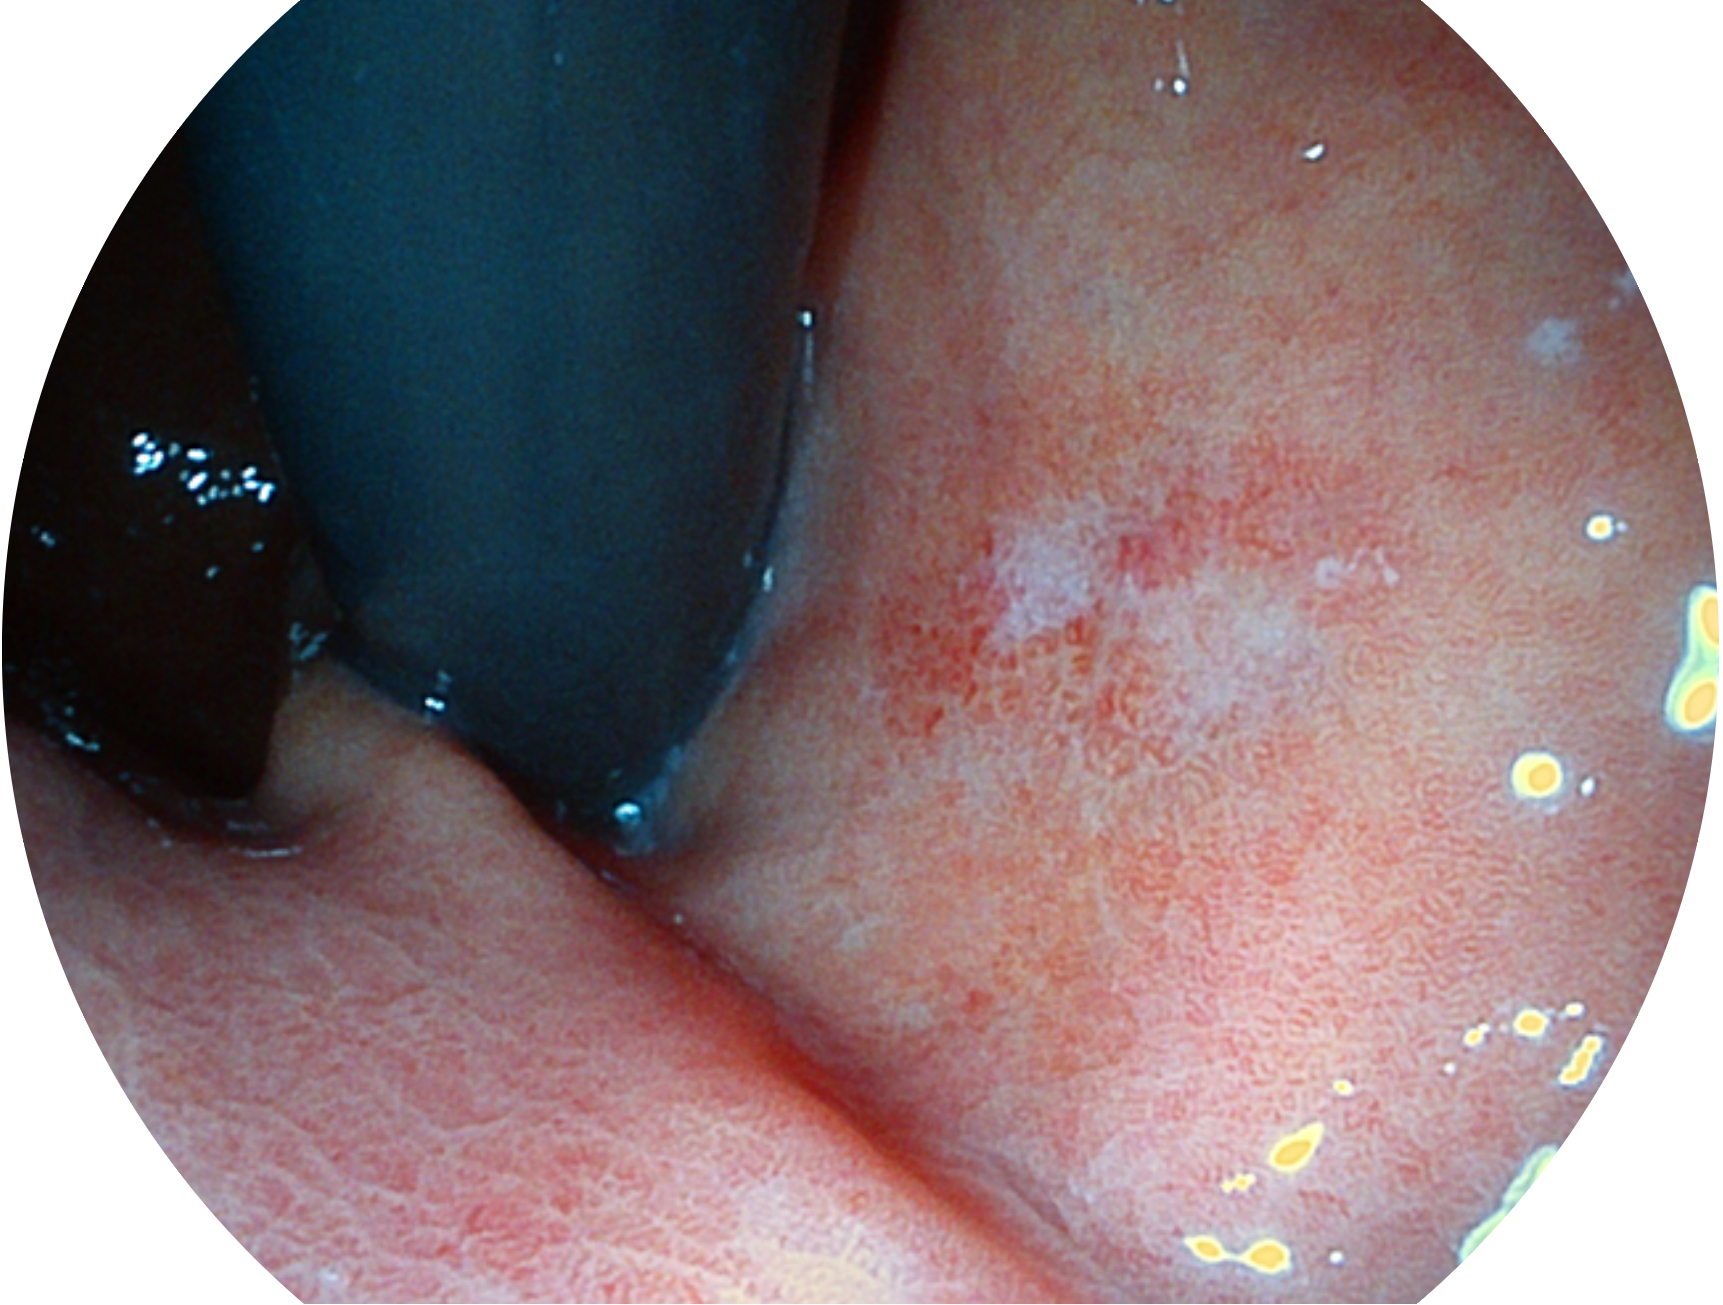

亚星官网新开发的内镜染色技术,主要是基于多波长LED 光源的开发,VLS-55Q 四波长LED 光源是由四个不同颜色的LED光按照相应照明模式所规定的特定发光比例进行合束后形成,合束后形成的照明光的光谱由红光、绿光、蓝光及蓝紫光这四个不同的波段范围构成。具有更高光谱自由度,通过光谱比例的控制,实现了聚谱成像技术,英文全称为“Spectral Focused Imaging, SFI”,缩写为“SFI”和光电复合染色成像技术,英文全称为“Versatile Intelligent Staining Technology, VIST”,缩写为“VIST”。